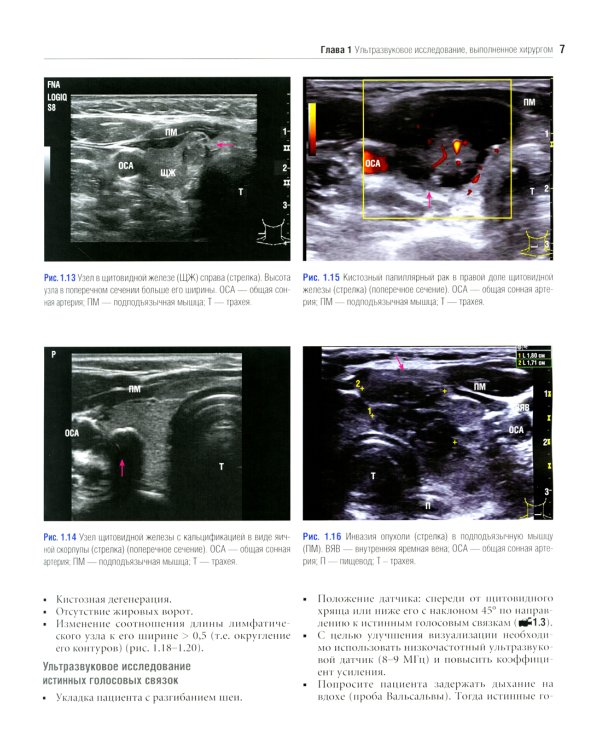

Данное издание представляет собой великолепно иллюстрированный хирургический атлас. В нем рассмотрены методы ультразвукового исследования шеи, молекулярно-генетическое тестирование пациентов с узловыми образованиями в щитовидной железе, робот-ассистированные хирургические методы, техника эндоскопических операций при эндокринных опухолях, хирургия при рецидиве заболевания, аутотранснлантация и криоконсервация околощитовидных желез, адреналэктомия при метастазе в надпочечнике, хирургия нейроэндокринных опухолей тонкой кишки и их метастазов в печени. «Атлас эндокринной хирургии» состоит из 4 частей: «Хирургия щитовидной железы», «Хирургия околощитовидных желез», «Хирургия надпочечников», «Хирургия опухолей поджелудочной железы и карциноидов». Всего в издании 29 глав, подготовленных сотрудниками экспертных факультетов ведущих медицинских школ США, Европы и Азии. Каждая глава состоит из разделов, в которых описаны общие сведения, показания и противопоказания, оценка риска, алгоритм принятия решений и планирование вмешательства, необходимое оборудование и материалы, хирургические техники, результаты лечения, осложнения и последующее наблюдение, а также даны советы и предостережения авторов. В книге много информации, которой нет в других источниках. Наряду с многочисленными фотографиями, сделанными в ходе операций, а также данными, полученными при различных методах визуализации, приведено значительное количество иллюстраций и видеоматериалов, демонстрирующих хирургическую технику или обследование. Издание предназначено практикующим врачам в области эндокринной хирургии, специалистам в смежных областях медицины и студентам медицинских высших учебных заведений.| Издательство | Логосфера |